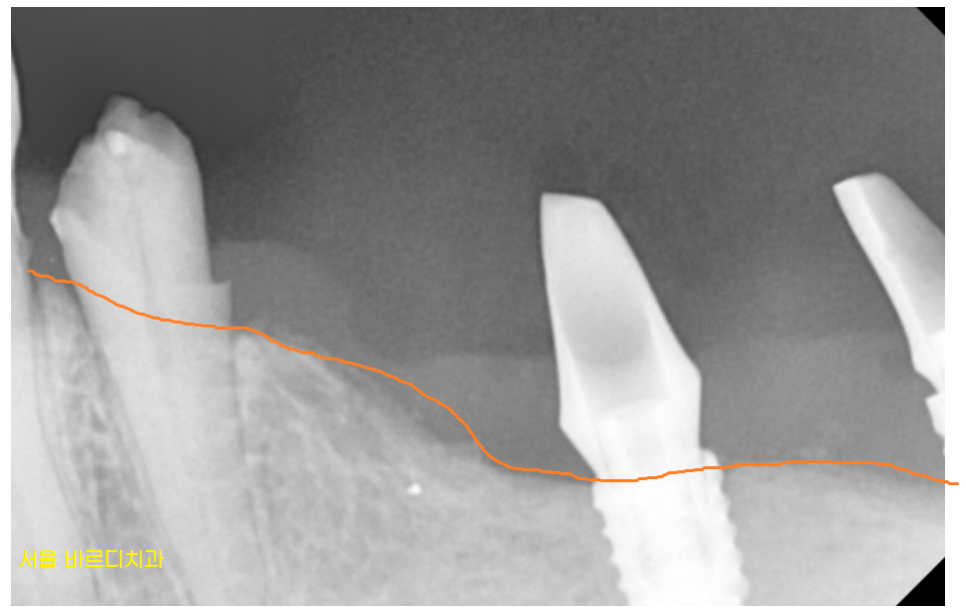

망월동 치과에서 발치후

왼쪽 아래 임플란트 먼저 수술하였습니다.

기존에 있는 임플란트를 제거 후

교체해주는 작업을 진행하였습니다.